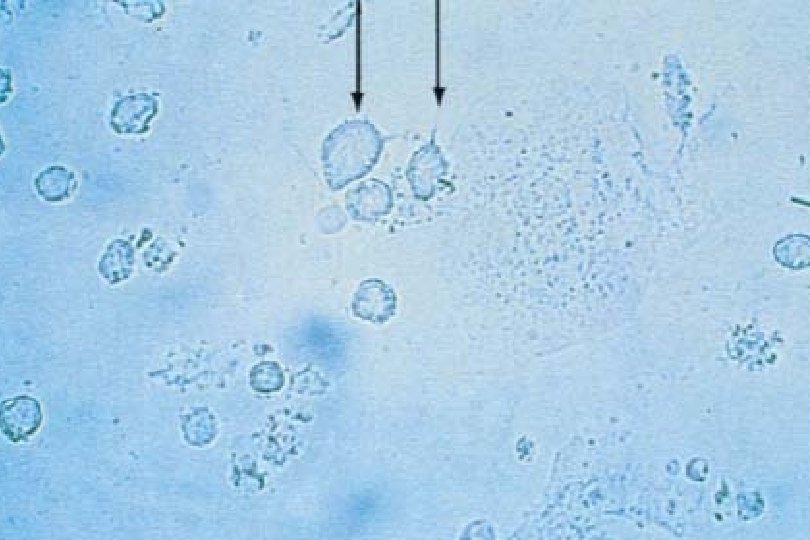

Trichomoniasis: The Basics • Etiology: Trichomonas vaginalis • Sexually transmitted ? colonic reservoir • Mostly asymptomatic • Male partners generally asymptomatic; sometimes NGU • Saline mount insensitive (~50 -60%) Culture ~70%; PCR requried to detect >90% of cases • Male partners generally asymptomatic; sometimes NGU